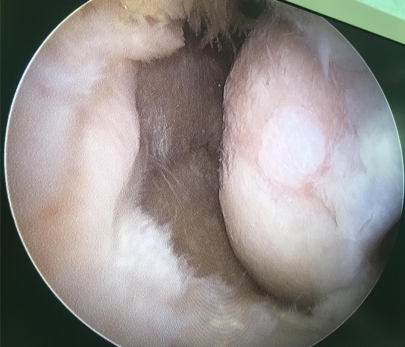

膝关节退行性病变

退行性半月板病变部分切除术